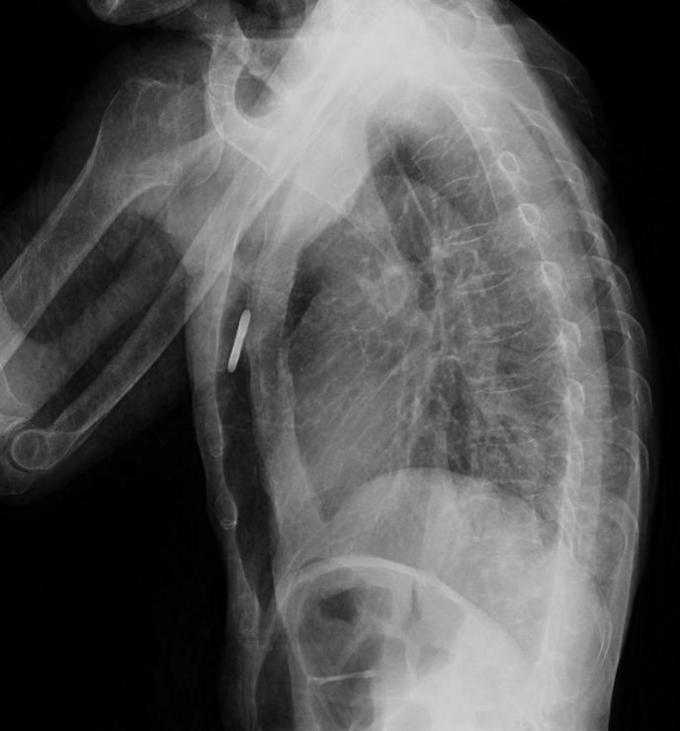

钡餐误吸

男性,61岁吞咽困难1月 进行性吞咽困难,无饮水呛咳,无发热,无咳嗽 咳痰

患者白日行钡餐检查,夜间出现呼吸困难,血氧饱和度下降,考虑存在1型呼吸衰竭 讨论: 1.目前针对钡餐误吸性肺炎的治疗措施哪些有意? 2.如何预防本次事件?